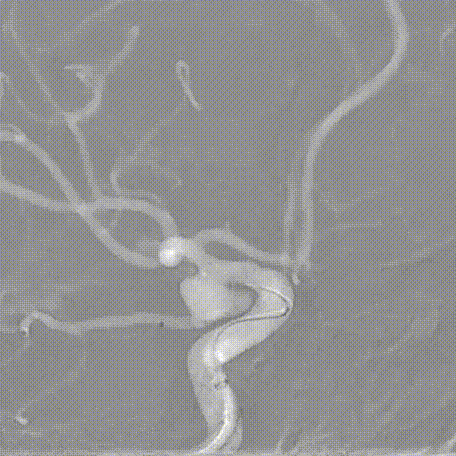

右侧颈动脉正侧位造影:可见原始胚胎型大脑后动脉。

左侧颈动脉正侧位造影:左侧颈内动脉后交通段动脉瘤(箭头所示)。

左侧颈内动脉3D造影可见动脉瘤位于后交通动脉起始处。

3D血管造影可见左侧后交通动脉瘤,大小约7.05×7.47mm,瘤颈3.68mm,考虑胚胎型大脑后动脉。